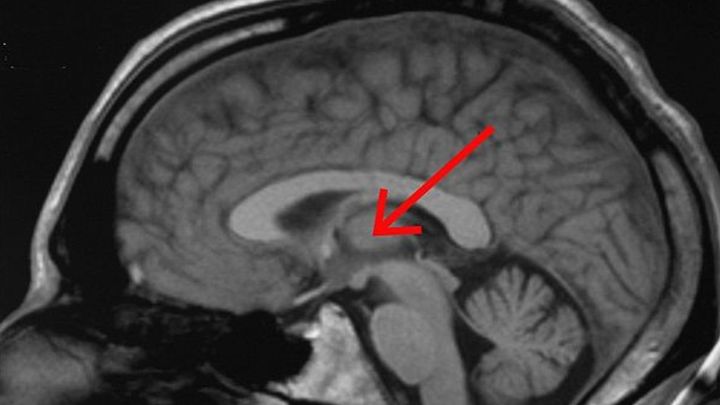

スイス・ジュネーブ大学の研究チームは、脳の視床と呼ばれる部位が単に感覚信号を中継するだけでなく、まるで「感度を調節するダイヤル」のように働いていることを明らかにしました。

脳内に入った感覚情報は、まず「視床」という中継地点に送られ、その後、大脳皮質の体性感覚野という部位で初めて意識される「感覚」として知覚されます。

視床はしばしば、感覚情報を皮質へ送る前の重要な「中継駅」にたとえられ、これまではどちらかといえば受け取った信号をそのまま次に伝える、いわば受動的な役割が強調されてきました。

脳の中にあった感覚の『ボリューム調整つまみ』 / Credit:wikipedia

視床と感覚調整の謎が解けた!自閉症や意識の理解にも光 / Credit:川勝康弘